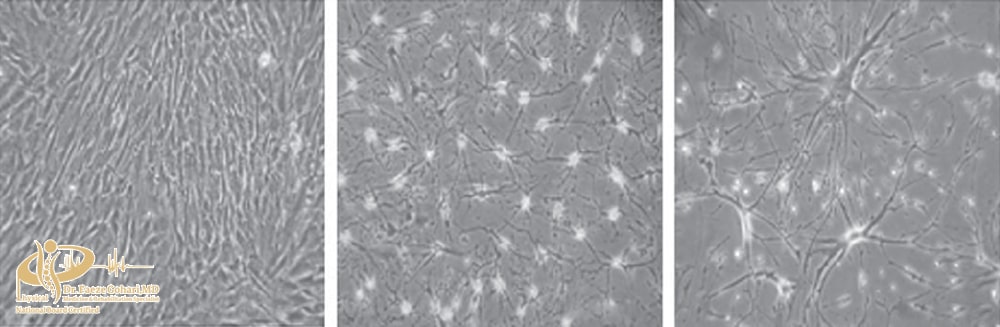

رشد سلولهای بنیادی بالغ (مزانشیمی) در آزمایشگاه: ابتدا سلولها بهصورت کشیده و منظم رشد میکنند (چپ)، اما باگذشت زمان، شکل آنها تغییر کرده و بهصورت ستارهای یا شبکهای درمیآیند (وسط و راست) که نشاندهندة فعالیت و آمادگی آنها برای تبدیل به بافتهای مختلف است.